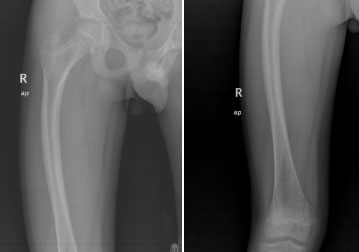

上圖為患者12歲時(shí)第3次股骨干骨折影像學(xué)資料

上圖為患者右側(cè)股骨干弓形變影像學(xué)資料